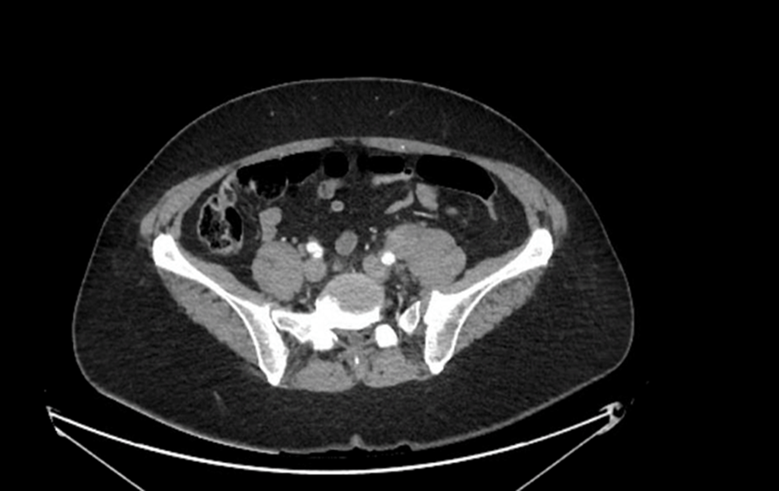

Open AccessClinical Case

Primary Lung Cancer Versus Metastasis of Thyroid Cancer the Utility of FDG PET CT

Sánchez-Ríos Carla Paola, Guzmán-Casta Jordi, Riera-Sala Rodrigo Fernando, López-Vratny Claudia, Hernández-Dehesa Itzel Ariadna, González-Araujo Andrea, Correa-Cano Rafael, Peña-Mirabal Erika, Aguirre-Pérez Natalia, Ayala-Domínguez Adriana, Elvira-Fabián Karina, Carrasco-Cara Chards Sonia, Martínez-Barrera Luis Manuel, Rodríguez-Cid Jerónimo Rafael, Alatorre-Alexander Jorge Arturo

International Journal of Innovative Research in Medical Science·December 12, 2020